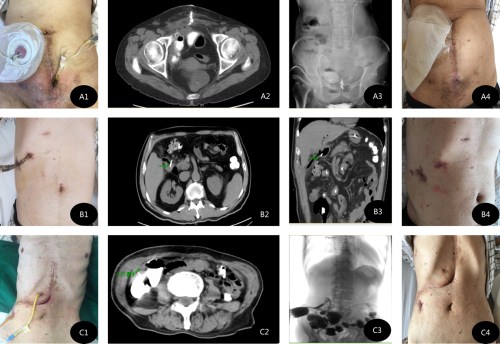

附:2016年7月,随着李元新主任加盟北京清华长庚医院普通外科,短短4月时间内,已陆续诊治患者近百例,其中肠外瘘患者占三分之一。在其中有3例为肠瘘发生早期直接转入我科的,经过积极的处理、反复的评估、利用猪源纤维蛋白胶有效的封堵,3位患者已自愈出院。

A1:膀胱癌根治、回肠代膀胱术后小肠瘘患者。A2/3:造影+CT评估窦道情况。A4:经过2次堵胶,肠瘘自愈

B1:腹腔下胆总管切开取石术后十二指肠瘘患者。B2/3同A2/3。B4:经过1次堵胶成功

C1:胆囊脓肿、切除术后结肠瘘患者。C2/3同A2/3。C4:经过2次堵胶,肠瘘自愈